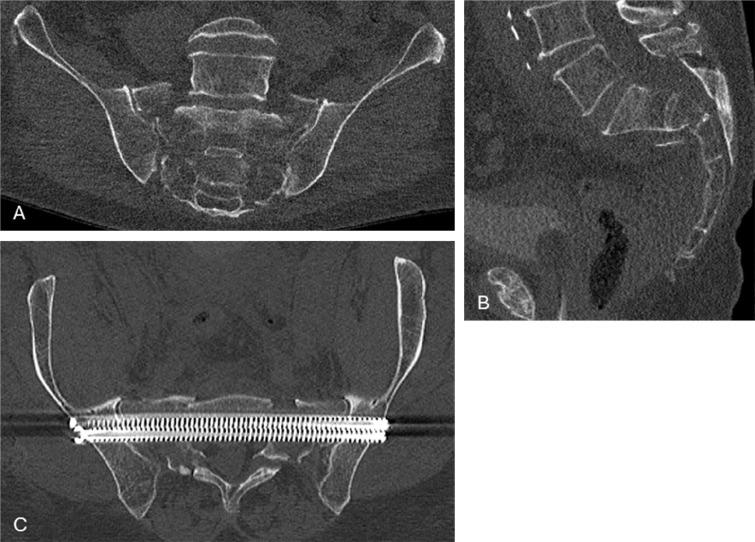

A 73-year-old patient with a complex sacral fracture underwent stabilising orthopaedic surgery. Postoperative brain CT showed fat droplets in the subarachnoid space and lateral ventricle. These fat droplets migrated into the cerebrospinal fluid by a tear in the sacral thecal sac. Teaching point: Intracranial subarachnoid fat droplets may be observed after spinal surgery.

一位73岁的复杂骶骨骨折患者接受了稳定骨科手术。术后脑CT显示蛛网膜下腔及侧脑室有脂肪滴。这些脂肪滴通过骶鞘囊的裂口迁移到脑脊液中。教学点:脊柱术后可观察到颅内蛛网膜下腔脂肪滴。